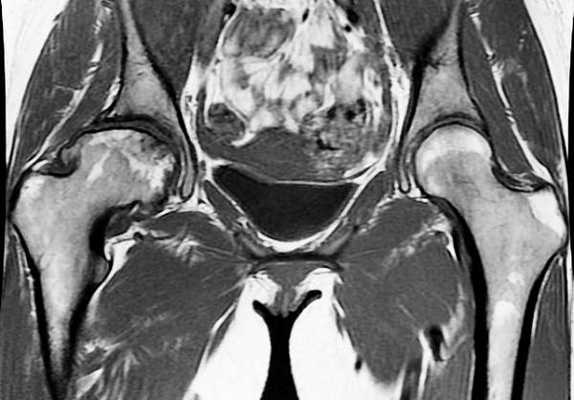

МРТ костей таза показывает множественные очаги, что говорит о метастатическом поражении